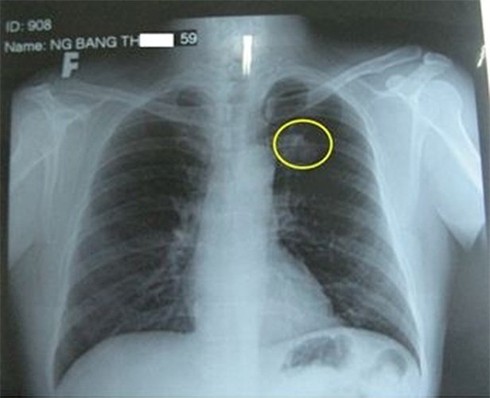

Phát hiện u phổi, làm sao để biết có phải ung thư không?

Phát hiện u trong phổi, muốn biết u lành hay u ác thì phải kiểm tra như thế nào?

Bạn nên đưa bố đi khám ở cơ sở ung bướu để đánh giá toàn thể, cơ quan hô hấp cũng như các cơ quan khác. Chẩn đoán ung thư phổi cần phải sinh thiết mới có chẩn đoán cuối cùng.